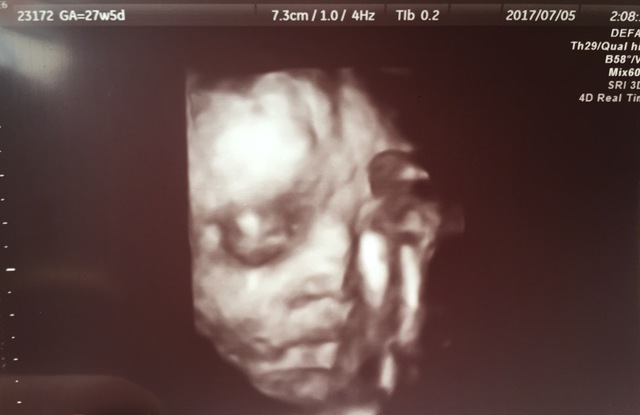

27週4日(27w4d・男の子)|rearea0404 さん(35歳)

私にとっても似ていて、おなかにいるのにリアルにうつってるので、母と最近の技術者は凄いなぁと話してました。生まれてきた赤ちゃんとほぼ同じでした。鼻はとてもリアルに似ていました。手の位置など生まれてからも、寝るときはその位置に置いて寝るので本当に凄いです。